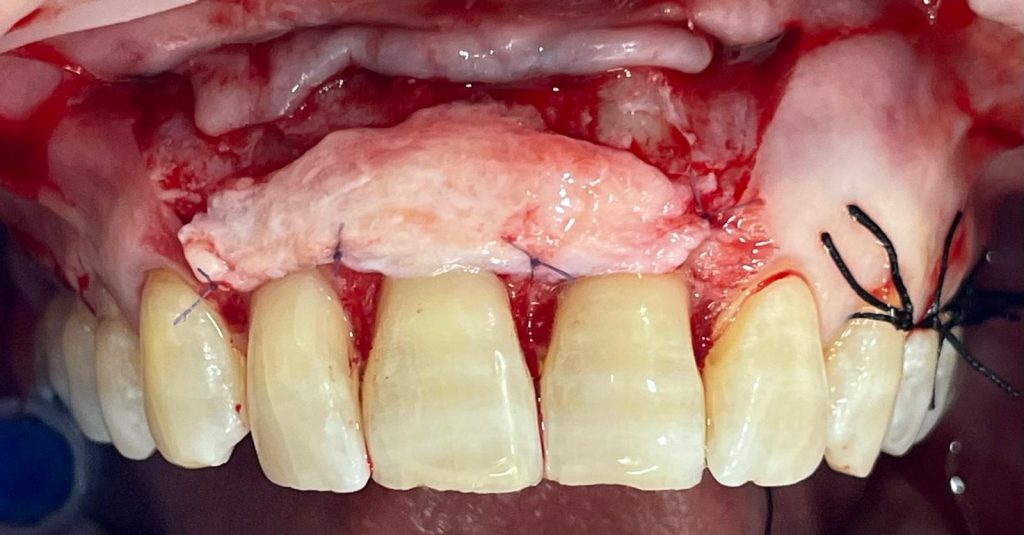

Il secondo caso del mese presenta un bellissimo intervento di chirurgia mucogengivale del gruppo frontale superiore con innesto di tessuto connettivo prelevato dal palato con la tecnica dell’incisione singola e coperto con CAF.